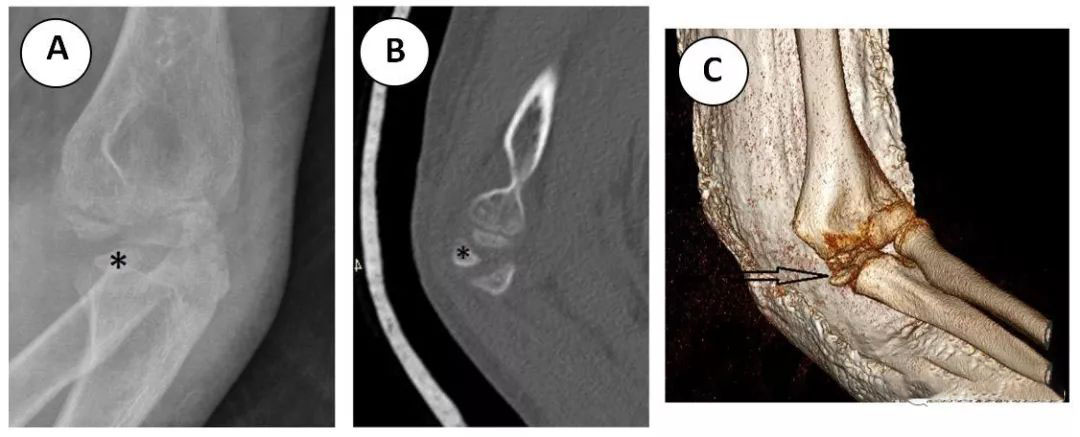

肱骨内髁骨折在儿童肘关节骨折中占第三位,约 10%。10 肱骨内上髁是一隆起,是屈肌腱的共同附着部位。内上髁骨折发生在青少年早期,相对于髁上、外髁骨折人群,内上髁骨折发生的年龄偏大。患者摔倒后伸肘,导致肘部急性外翻应力。外翻应力引起内上髁撕脱性骨折,由屈肌腱和旋前肌腱共同作用导致 (图 7)。13 由于内上髁是一个关节外骨结构,肱骨内上髁骨折往往不会导致关节积液 (图 7B)。其中,30%-50% 的内上髁骨折与肘关节脱位有关。14 当肘关节脱位时,内上髁撕脱,有时夹在肱尺关节内 (图 8A)。放射科医师必须认识这种复杂的骨折,以避免延误诊断和防止肘关节破坏。CT 可用于确定向肱尺关节内移位的内上髁,特别是在未完全骨化和 (通常) 碎片化的滑车骨化中心的潜在混乱环境中 (图 8B 和 C)。肱骨内上髁骨折的处理取决于移位的程度。如无移位或移位小于 5mm,则石膏制动治疗。如骨折块移位大于 5mm 或夹在肘关节内,则最好采用切开复位穿针内固定。14,15

图 8 一个 12 岁的男孩在学校上体育课时摔倒了。(A) 肘部 x 线片斜位显示尺骨 - 滑车沟撕脱性内上髁 (星号) 骨折。(B) 矢状位 CT 和 (C) 肘部轴向薄层 CT 三维重建显示,在尺骨滑车沟内也发现了类似的内上髁 (星号,箭头)。可见内上髁上方未分化、正常、碎片化的滑车骨化中心。